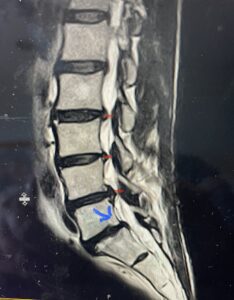

(Fig. 2) T2-weighted lumbar MRI demonstrating severe lumbar stenosis (red markers) and a grade 1 spondylolisthesis at L5-S1 (blue arrow)

This 59 year-old female had severe bilateral leg pain and numbness over a 6-month period. The patient had failed conservative treatment with physical therapy, chiropractic care, and medications. MRI revealed that she had severe lumbar stenosis with a grade 1 spondylolisthesis or “slipped disc” at L5-S1 (Fig. 2).  In addition, she had previously undergone both front and back surgery for severe cervical stenosis where her posterior hardware had failed because of her severe osteoporosis requiring us to remove the posterior hardware.  This required her to have an anterior or front operation which allowed better fixation to her spine because of the load-sharing nature of the interbody grafts in addition to her anterior cervical plate (Fig. 3).